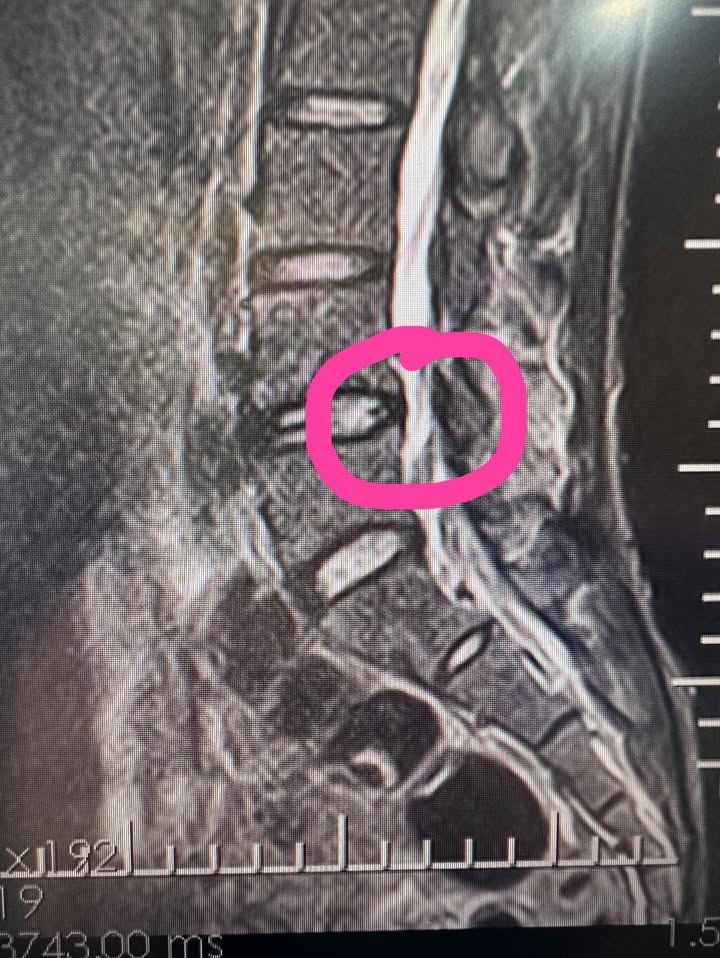

新北新北淡水陳先生,年紀大概36歲,當初因為腰椎的問題,他提到他想要再次去爬山,問題沒有特別嚴重,但就是一般的復健針灸效果不如預期反反覆覆,一到直到我幫他安排核磁共振才發現他第四節的腰椎椎管有一點狹窄,加上他長期久坐,所以腰椎退化的比較快,療程進行得很順利,在畢業一段時間後收到他去爬大山的照片,真的是太棒了